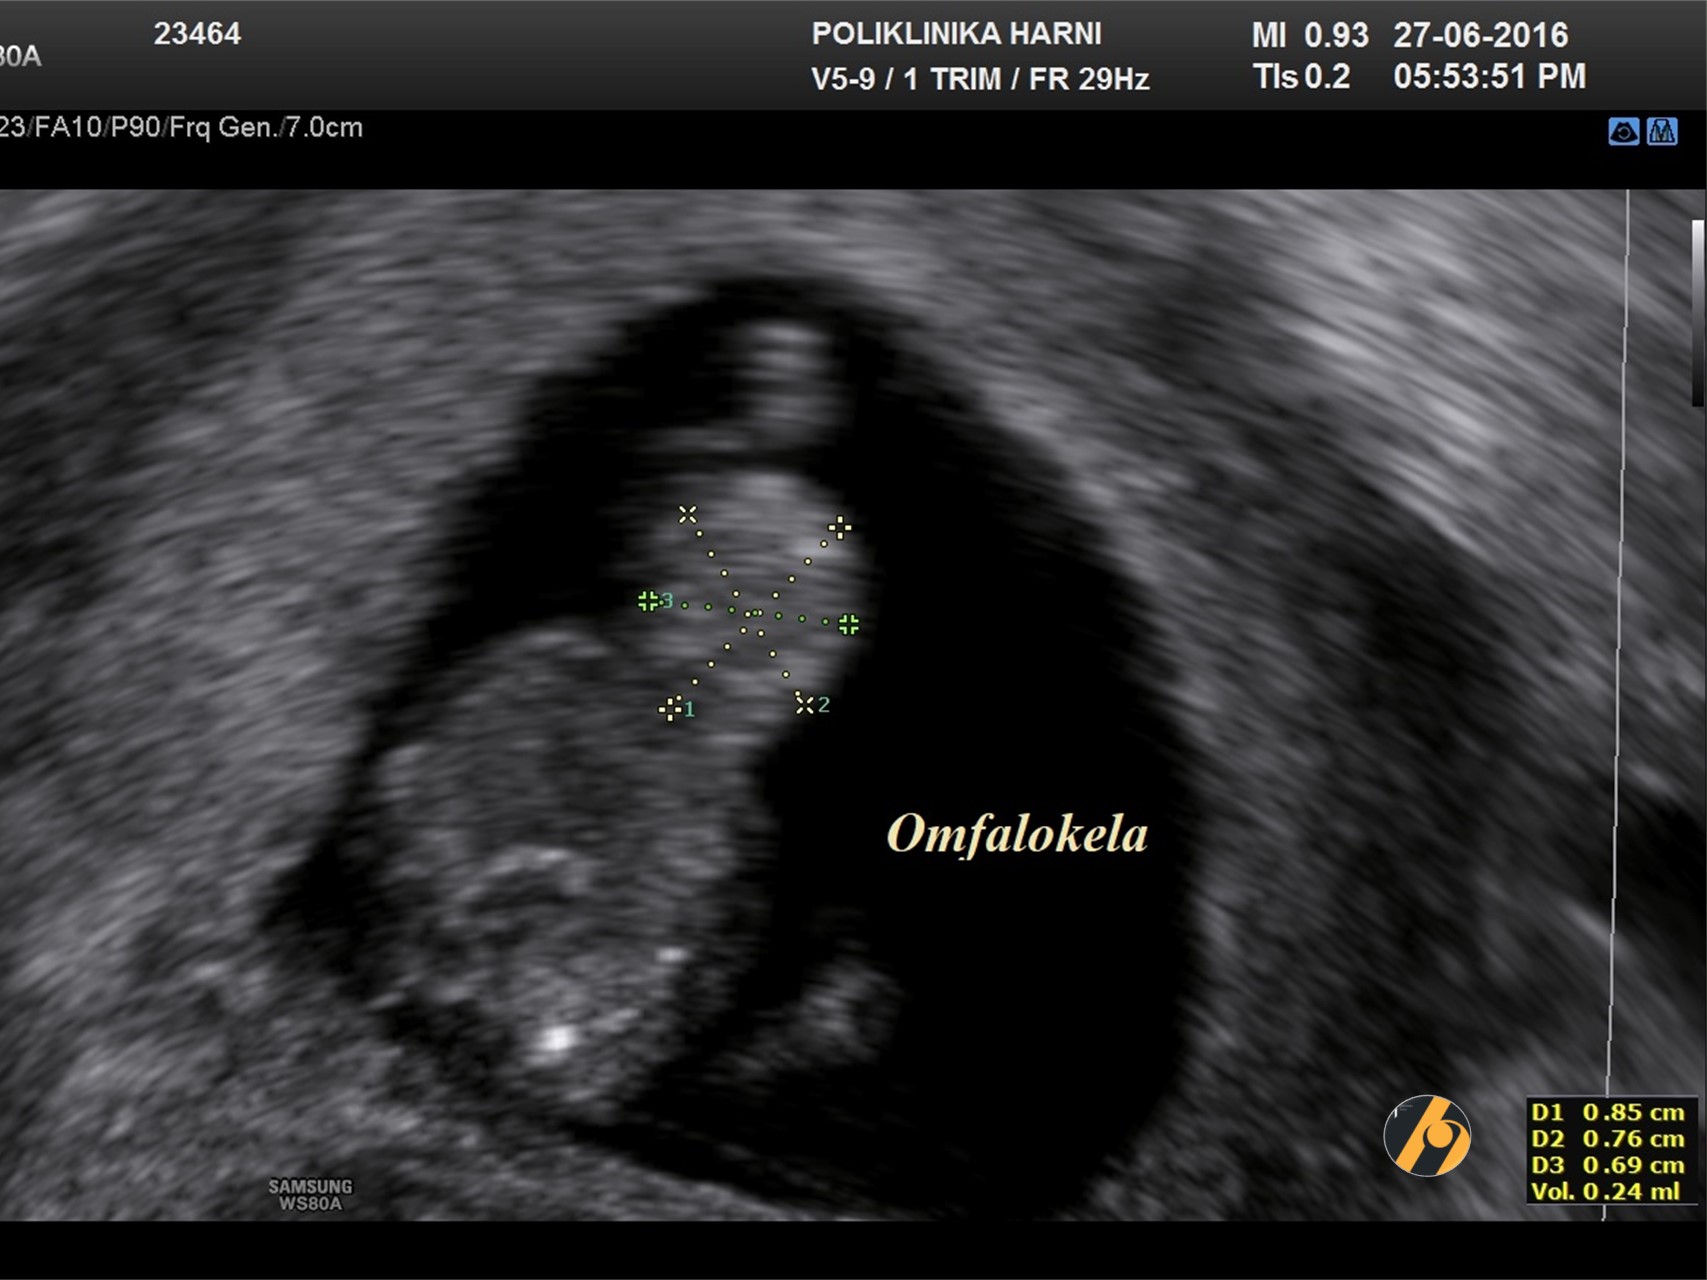

S 8-10 tjedana svi fetusi pokazuju hernijaciju tankog crijeva koja se vizualizira kao hiperehogena masa u bazi pupkovine. Retrakcija u abdomen se događa između 10.-12. tjedna trudnoća, a završava do 11 + 5 tjedana.

U 11.-13. tjednu trudnoće pojavnost omfalocele je oko 1 na 1,000, što je četiri puta veće nego kod živorođenih. Stanje je obično sporadično. Učestalost kromosomskih anomalija, uglavnom trisomije 18, iznosi oko 60%, u usporedbi s 30% u sredini trudnoće i 15% u novorođenčadi, jer je trisomija 18 povezana s velikom stopom intrauterine smrti.

Rizik kromosomskih anomalija je veći ako omfalocela sadrži samo crijevo bez jetre. Povećani nuhalni nabor nalazi se u otprilike 85% kromosomski nenormalnih i 40% kromosomski normalnih fetusa s omfalocelom.

Na slici je prikazana omfalokela u 12. tjednu trudnoće, udružena s generaliziranim fetalnim edemom.